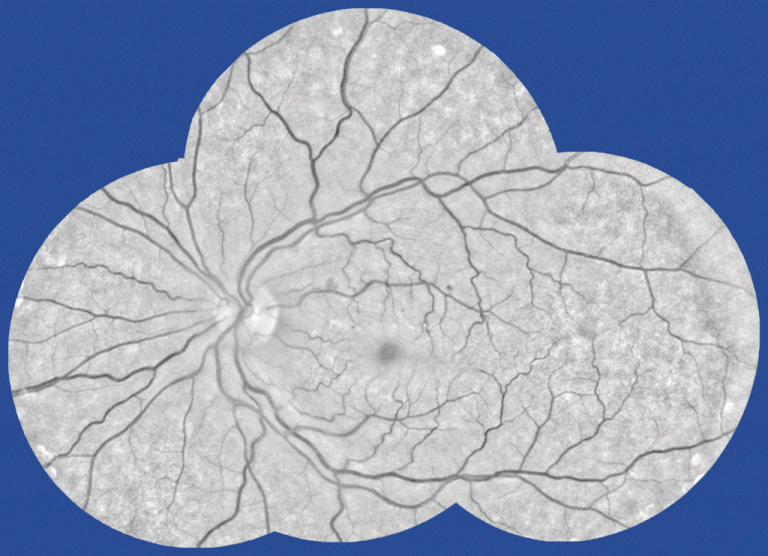

Fundus photo. (Photo: Eye Hospital Rotterdam)This is done by taking retina or ‘fundus’ photos and depending on the analysis of the photos, the expert will either schedule a follow-up examination or refer the patient to an ophthalmologist (eye specialist).

- Normalisation of the illumination (converting the orange image into a high contrast image with grey tones).

- The Rotterdam Eye Hospital’s protocol is to take four images (top, bottom, left, right) for each eye to show the maximum surface of the retina. Image processing merges the four images into a single mosaic by zooming, rotating, translating, and assembling the images onto a fixed register.

1: fundus mosaic, 2. white spots mark differences, 3. red marks on clinical relevant changes. (Gif: Kedir Adal)